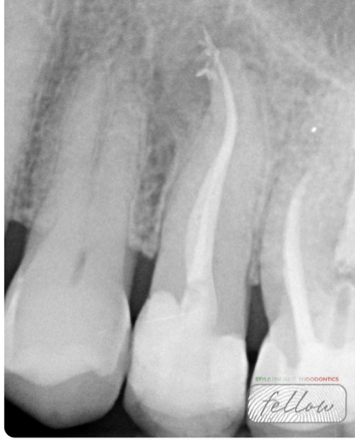

Fig. 3

Following local anesthesia, the pulp chamber was opened, revealing purulent exudate. Proper root canal shaping is crucial, particularly in necrotic teeth, as it allows irrigants to penetrate deeply, exert antimicrobial effects, and dissolve organic debris. Proper shaping also facilitates the effectiveness of sodium hypochlorite, enhancing pulp tissue dissolution and thorough canal cleaning.

Fig. 4

Root canal shaping was performed using a combined rotary system to achieve optimal shaping and apical enlargement while preserving the original canal anatomy: Mtwo rotary files and ProTaper Gold finishing files.